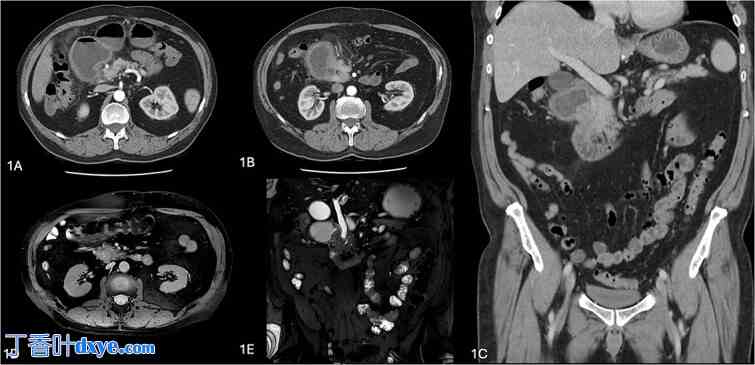

患者入院接受进一步检查。计算机断层扫描 (CT) 扫描显示十二指肠出口梗阻,胰头水平有一转变点,十二指肠周围脂肪条带和十二指肠壁增厚,并有该部位十二指肠外侧胰腺组织强化的印象(图 1)。磁共振胰胆管造影 (MRCP) 显示十二指肠第二段因梗阻性壶腹部病变而管径突然转变,一条扩张的肝外胆管(9 毫米)穿过该病变(图 1)。胰管大小正常,周围无淋巴结肿大或胰腺实质血管包裹。他的肝酶和血清肿瘤标志物(碳水化合物抗原 19-9 (CA19-9)、癌胚抗原和甲胎蛋白)无异常。他的血清脂肪酶水平为 171 U/l。上消化道内镜超声检查 (EUS) 旨在评估梗阻性壶腹部周围病变(补充视频 1)。

图 1

环状胰腺的放射图像。(A–C) 计算机断层扫描图像显示十二指肠梗阻,胰头水平出现过渡点,十二指肠周围脂肪条带,十二指肠壁增厚,该部位十二指肠外侧胰腺组织增强。(C, D) 磁共振胆胰管造影图像显示十二指肠第二段的管径因梗阻性壶腹部周围病变(即环状胰腺)而急剧变化。